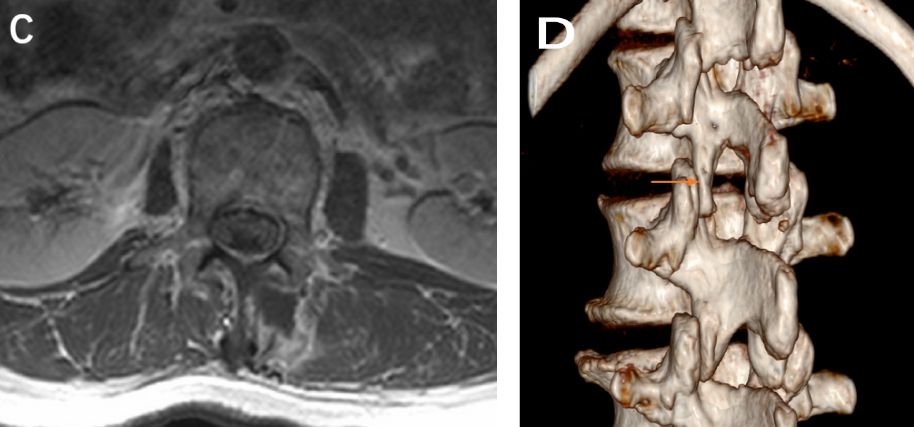

患者术后疼痛缓解,第2天下床活动。术后5天复查腰MRI(图4)未见肿瘤残留,左侧椎旁肌肉无明显损伤。术后病理(图5)提示(L1-2椎管内)神经鞘瘤。

图4. 术后腰椎增强磁共振及CT:A.B.C.术后增强扫描未见异常强化征象。D.术后VRT重建见腰1/2左侧微小骨窗,左侧关节突无破坏。